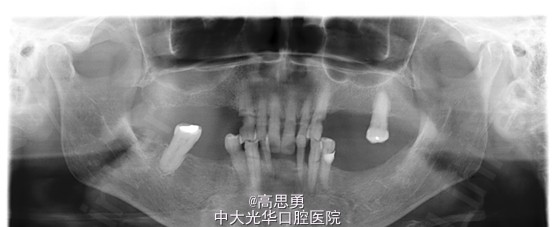

根尖X片示:13 根尖部阴影,牙颈部硬组织部分缺损

根尖X片示:13 根尖部阴影,根充可

1、牙列缺损(上颌肯氏II类I分类,下颌肯氏II类II分类)

2、#13慢性根尖周炎

3、#11、#12、#13、#21、#22、#23、#33、#42、#43、#44楔状缺损

4、慢性牙周炎